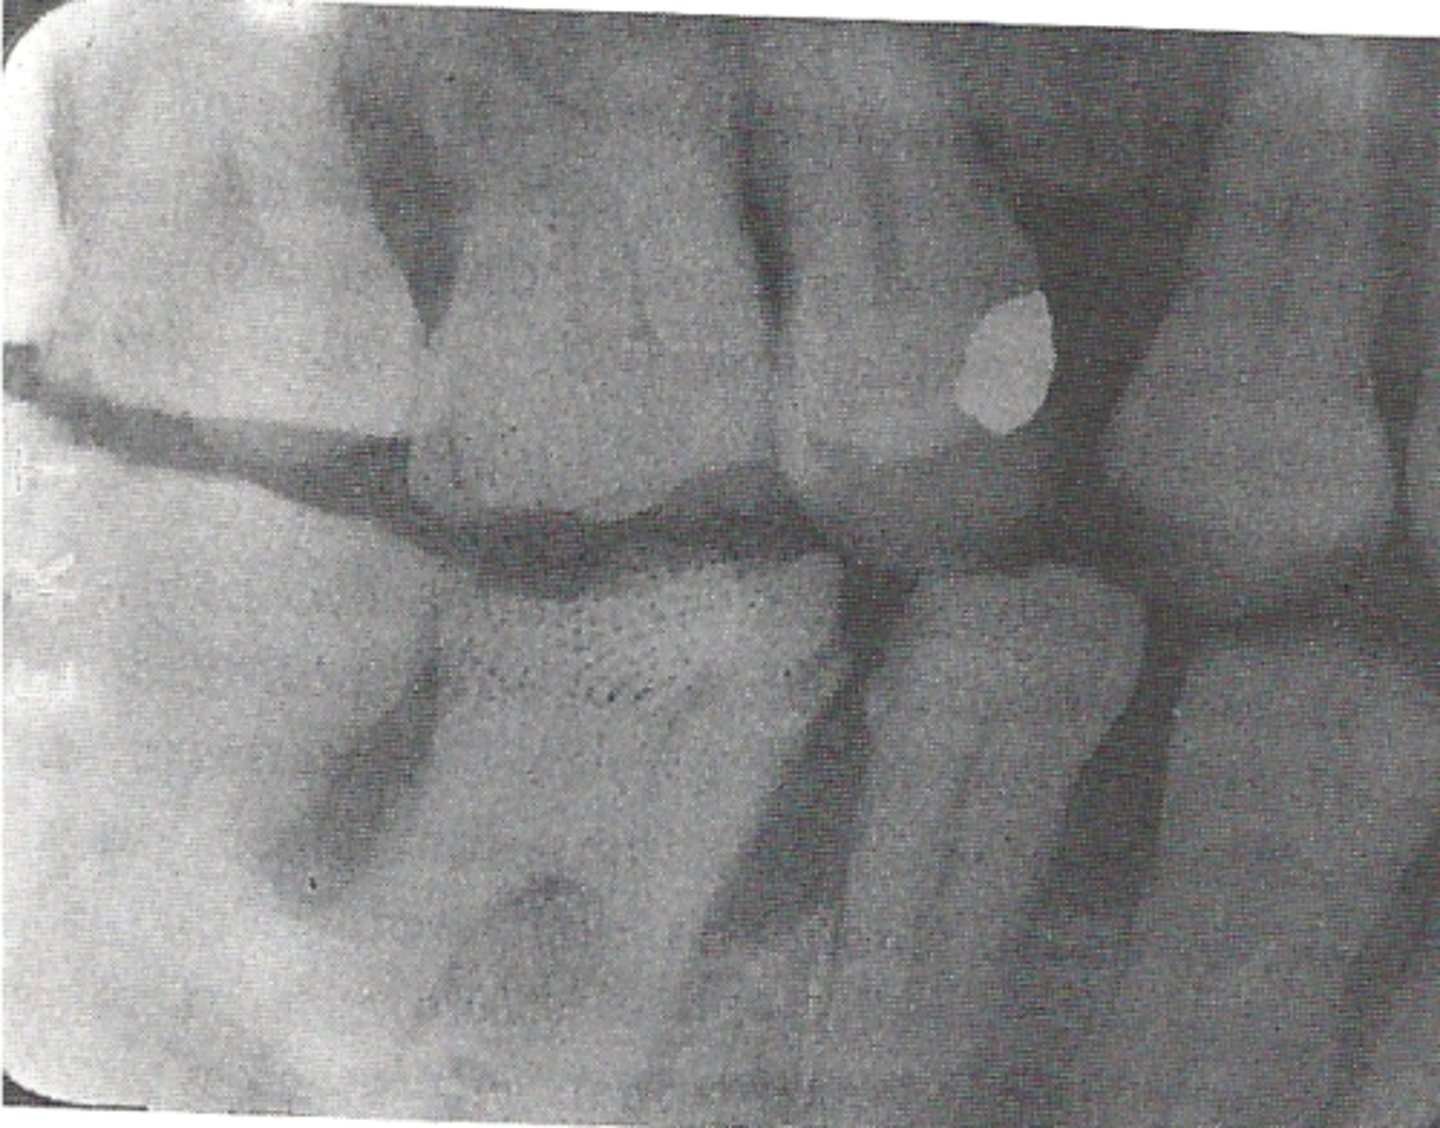

fingernail artifact error

when film emulsion is damaged by the operators fingernail

appears as a black crescent shape mark